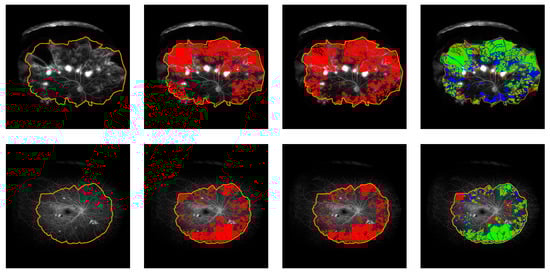

Figure 5.

Grid assessment examples. Left to right: FA image, grid annotation from grader 1, automated assessment, grid annotation from grader 2 (Kappa values. Ex. 1: Auto 0.80, Grid2 0.65; Ex. 2: Auto 0.93 Grid2 0.74; Ex.3: Auto 0, Grid2 0.08).

Agreement between concentric grid assessments is reported in Table 1. The circular grid assessment extracted from the automatic segmentation and the manual assessment provided by the first grader show an agreement of 0.55 (0.03) kappa. ICC of perfused and non-perfused segments are 0.89 (0.77, 0.93) and 0.86 (0.73, 0.92), respectively. When the grid assessment is performed on dense CNP annotations provided by the first grader, agreement with automatic assessment reaches 0.65 (0.04) kappa. In this case, ICC values are 0.90 (0.85, 0.94) for perfused segments, and 0.88 (0.81, 0.92) for non-perfused segments. Inter-grader agreement between manual assessment of CNP by the two graders on the circular grid shows 0.43 (0.03) kappa. ICC for perfused and non-perfused segments are 0.70 (0.48, 0.83) and 0.71 (0.48, 0.83). Results on the average number of perfused and non-perfused segments in each ring are listed in Table 2. Some examples are illustrated by Figure 5.